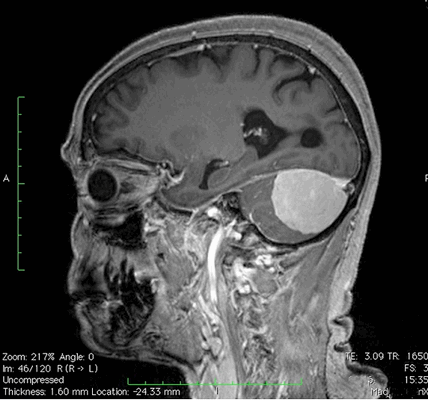

МР-сканирование при подозрении на менингиому мостомозжечкового угла, сагиттальная проекция